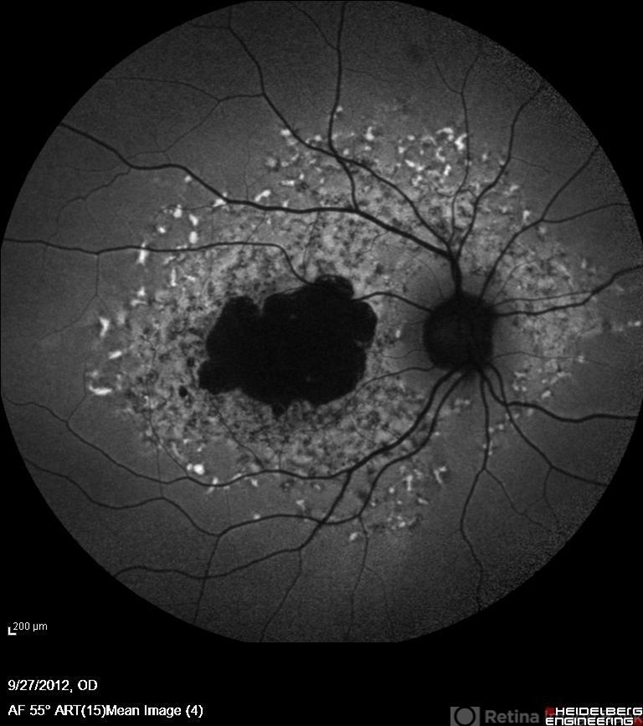

- Stargardt disease, autofluorescence imaging

- Autofluorescence imaging of the right eye of a 46-year-old man with decreased VA due to advanced Stargardt's disease.